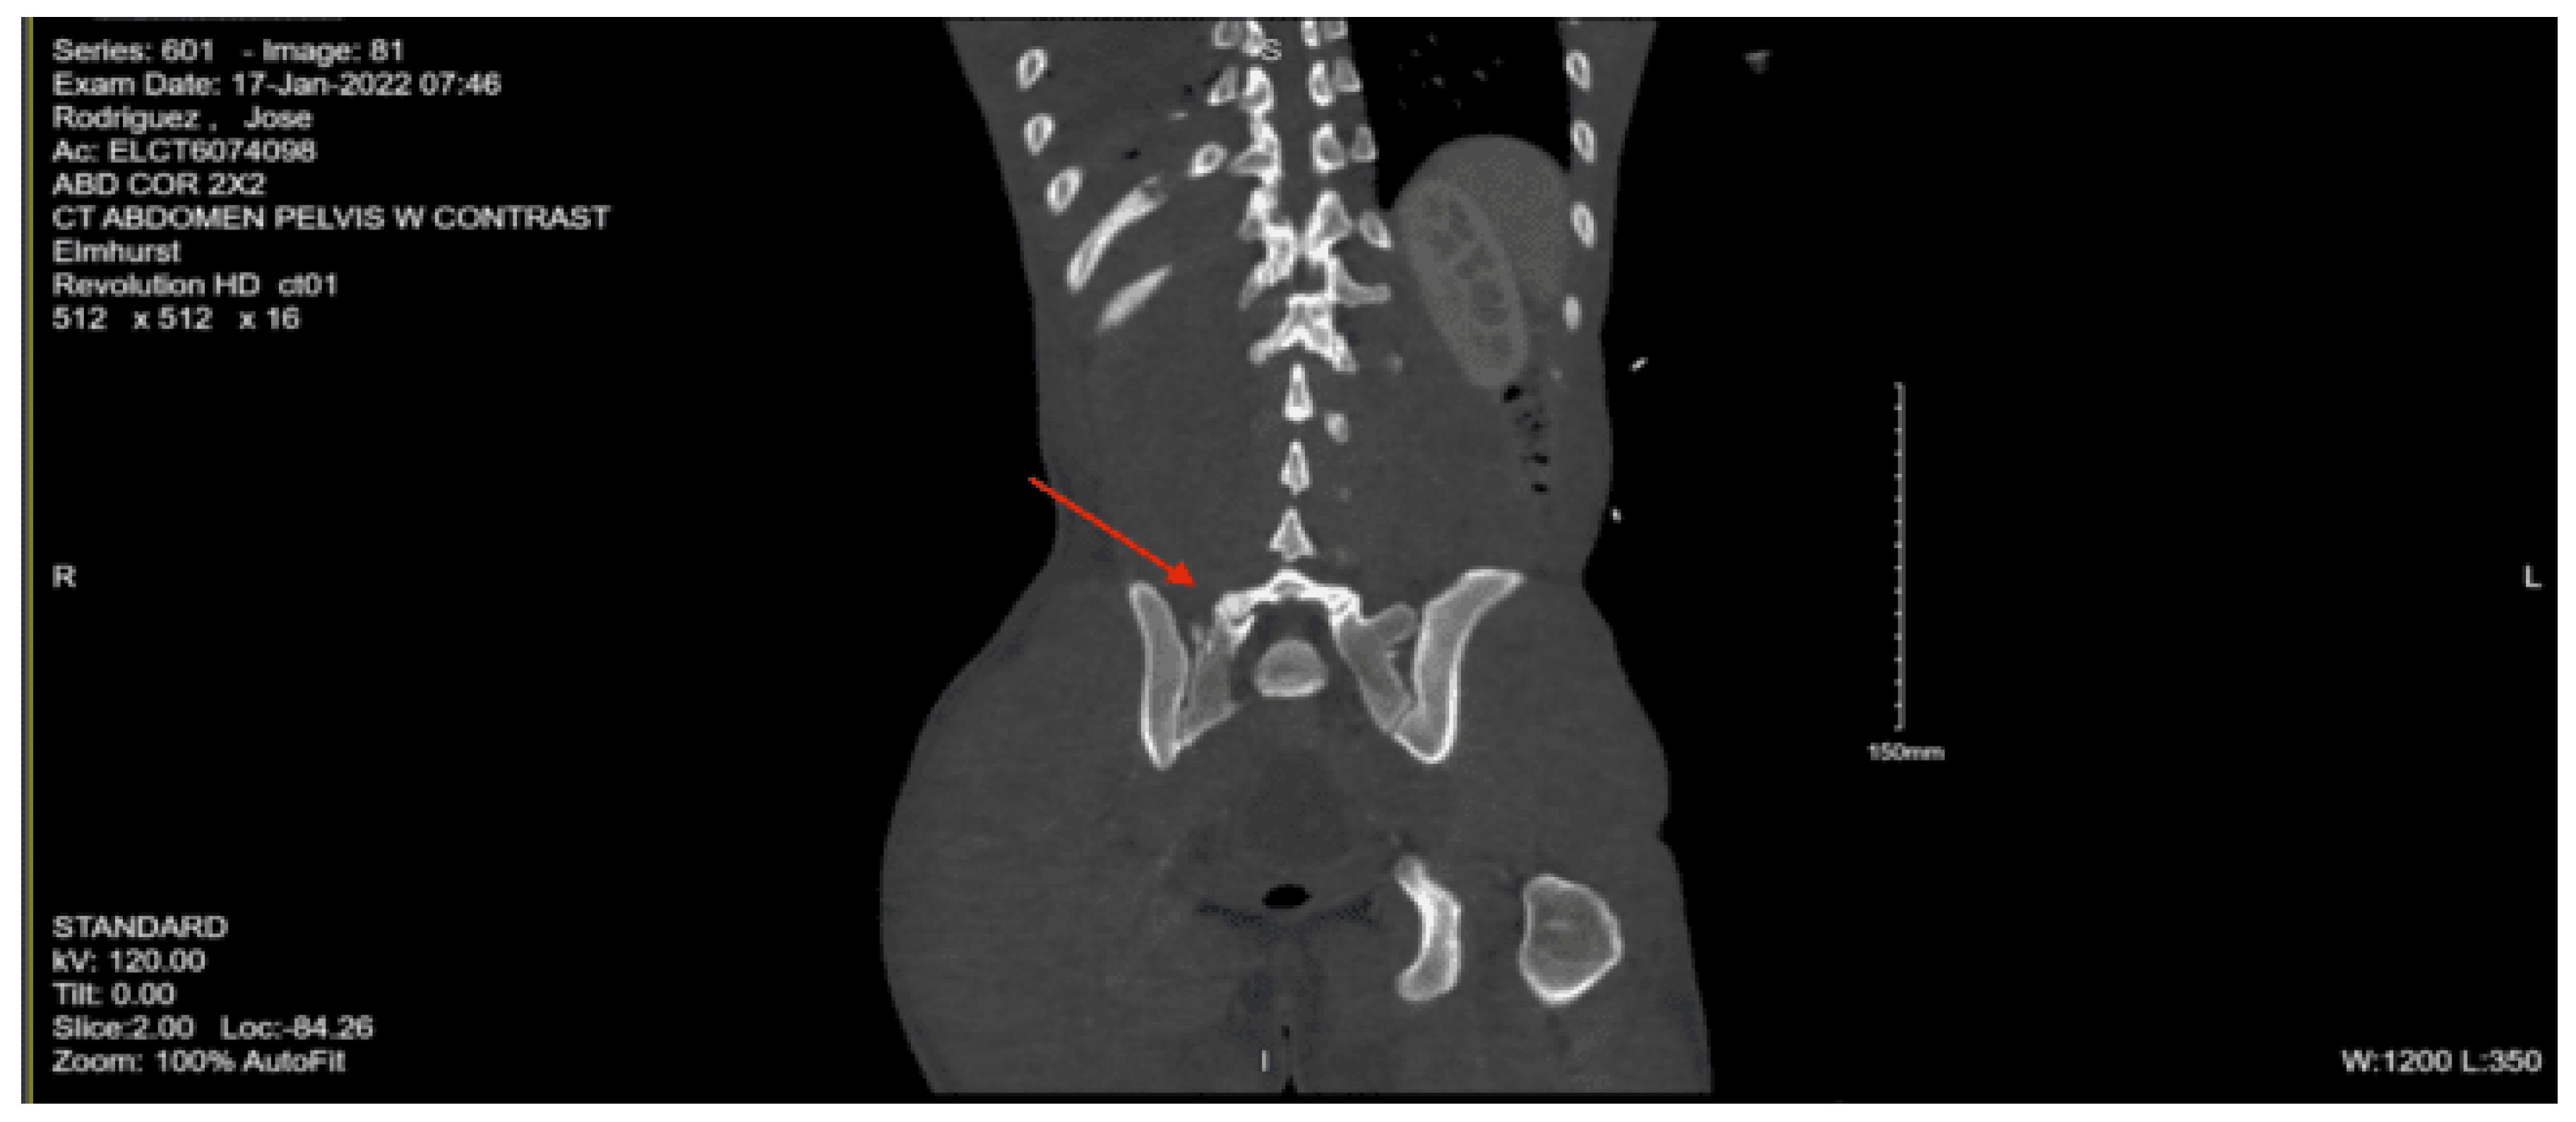

Imaging as shown in Figure 17 and Figure 18:

CT abdomen pelvis with contrast: Acute nondisplaced bilateral sacral alar fractures with extension into the sacroiliac joint on the right and probable involvement of the right S3 neural foramen. Amorphous hematoma in the medial left gluteal musculature and subcutaneous fat measuring approximately 3.3 x 6.6 x 7.7 cm. No visceral organ injury.